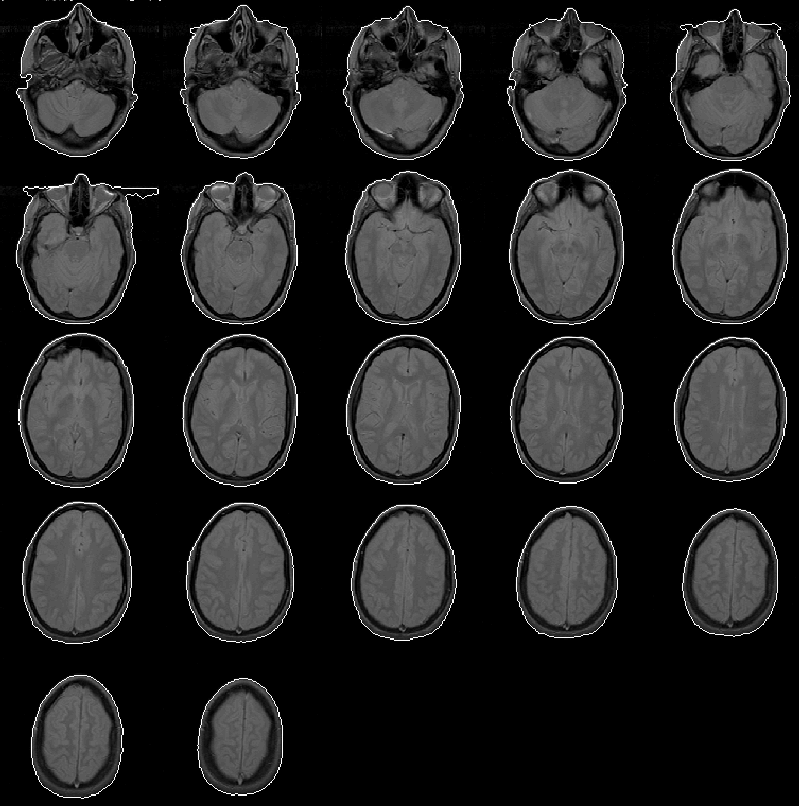

Figure 8.7 overlays the head mask produced for MRI Data Set 2 on the PD-weighted volume. The mask appears extremely accurate except for a region in slice 6 where the it extends outside the head. This error is caused by the of presence falsely placed data voxels due to phase-encoding problems in MR image reconstruction (see Chapter 2). This error might be reduced by low pass filtering or median filtering the volume before thresholding. As with the error occurring in Data Set 1, this error has little impact on the final results of the intracranial boundary detection algorithm and therefore has not been addressed.

Figure 8.7: The head mask for MRI Data Set 2 overlaid on the PD-weighted scan.